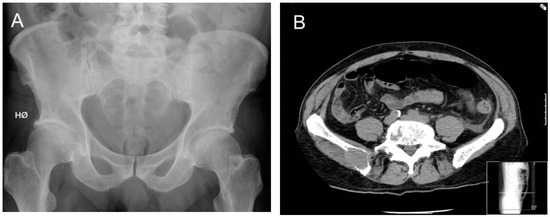

3.2. From Conventional Skeletal Survey to Whole-Body CT

- Edelstyn, G.A.; Gillespie, P.J.; Grebbell, F.S. The radiological demonstration of osseous metastases. Experimental observations. Clin. Radiol. 1967, 18, 158–162. [Google Scholar] [CrossRef]

- Hinge, M.; Andersen, K.T.; Lund, T.; Jørgensen, H.B.; Holdgaard, P.C.; Ormstrup, T.E.; Østergaard, L.L.; Plesner, T. Baseline bone involvement in multiple myeloma—A prospectiv prospective comparison of conventional X-ray, low-dose computed tomography, and 18flourodeoxyglucose positron emission tomography in previously untreated patients. Haematologica 2016, 101, e415–e418. [Google Scholar] [CrossRef] [PubMed]

- Hillengass, J.; Moulopoulos, L.A.; Delorme, S.; Koutoulidis, V.; Mosebach, J.; Hielscher, T.; Drake, M.; Rajkumar, S.V.; Oestergaard, B.; Abildgaard, N.; et al. Whole-body computed tomography versus conventional skeletal survey in patients with multiple myeloma: A study of the International Myeloma Working Group. Blood Cancer J. 2017, 7, e599. [Google Scholar] [CrossRef] [PubMed]